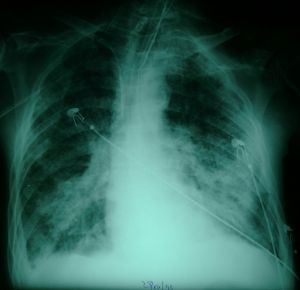

Before Recruitment

Arterial blood gas 18:00 23/10/1999 Fi0 2=70%

pH=7.47 pCO 2=31 pO 2= 59 Saturation 91

The above X-rays illustrate one of the most dramatic and successful

maneuvers you can perform in Intensive Care. The patient whose X-rays

are shown is a man in his sixties who had surgery for malignancy,

and subsequent to multiple complications including a deep vein

thrombosis, pulmonary embolism, and perineal sepsis, developed hypoxaemia

and bilateral pulmonary infiltrates, in the absence of clinical evidence of

elevated left atrial pressure. A recruitment maneuver produced

substantial improvement in his oxygenation, which was maintained.

By 23:00 on the same day he was weaned down to an FiO2 of

35% with the following blood gas:

pH=7.39 pCO2=35 pO2=69 Saturation 94